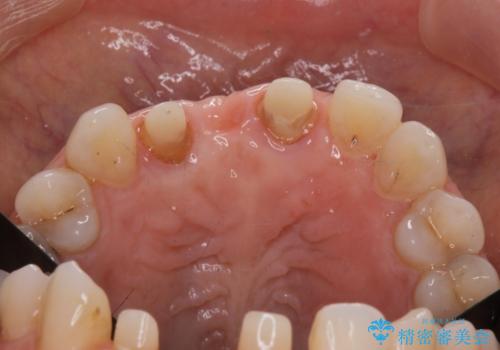

- 前歯のブリッジがすぐに外れる、歯ぐきが腫れている、見た目を良くしたい、と希望され来院されました。

現在装着されているブリッジを除去したところ、歯ぐきよりも上に存在する歯質(縁上歯質)が少なく、土台の形態の悪さや不適合などさまざまな問題があります。